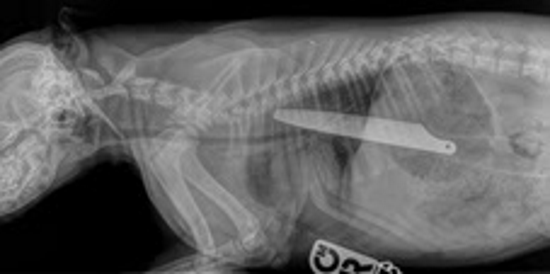

An eight-inch knife is clearly visible in the tiny puppy’s body.

The young puppy was admitted, and x-rays immediately revealed the severity of the situation. The knife handle had passed through Macie’s stomach and into her intestines, while the tip of the knife was still in her gullet. She underwent emergency surgery straight away to remove the knife while Irene, her partner and four children waited at home for news.

PDSA Vet, Emily Ronald, said: “I’ve never seen an x-ray like Macie’s. She was extremely lucky to survive. Her saving grace was that she swallowed the handle-end first – the blade-end would undoubtedly have pierced her organs, likely causing fatal injuries.